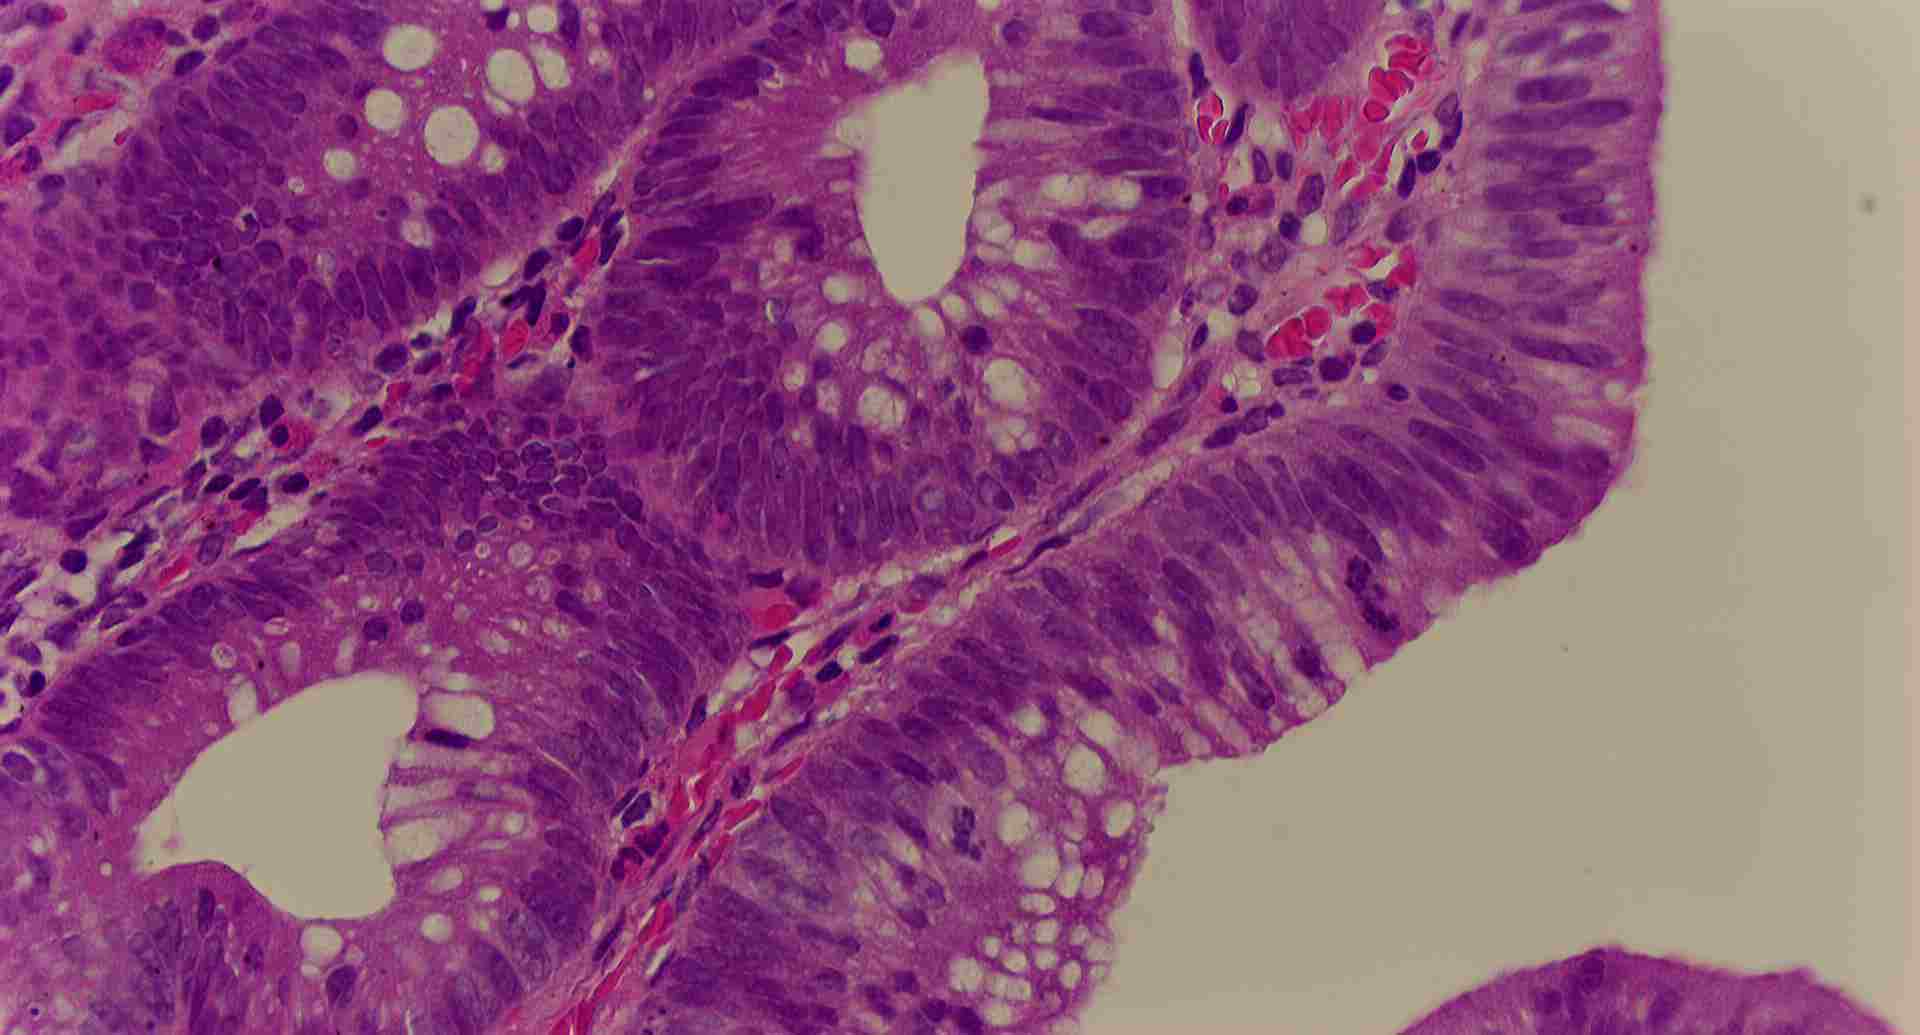

標本12